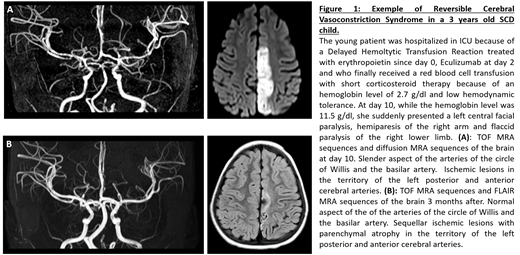

25 strokes occurred during the study period. 12 of them (48%) did not met the definition of a "typical" stroke related to sickle cell CV. The children with "atypical" stroke were older (9 years old +/- 4.6, vs 6.5 years old +/- 4.3 in the typical group, p = 0.0086) and less frequently of SS genotype (33% non-SS vs 8% non-SS in the typical group). They had lower leukocyte count (11.3 G/L +/- 4.6, vs 15.7 G/L +/- 2.3 in the typical group, p=0. 04) and higher hemoglobin level at the time of the stroke (11 g/dl +/- 3 vs 7.4 g/dl +/- 1.3 in the typical group, p= 0.027). 17% of atypical strokes had posterior ischemic lesions, 33% had anterior lesions and 17% had multiple systematized lesions, in counting junctional lesions. We also found 33% of ischemic lesions of the cerebellum. Considering a potential trigger of the stroke, 58% of atypical events were hospitalized in an anesthesia or intensive care unit at the time of the stroke or less than 7 days before, compared to 8% of children with a "classic" stroke (p= 0.011). The etiologies adopted by clinicians and radiologists for the atypical stroke were reversible cerebral vasoconstriction syndrome (RCVS) (Figure 1), cerebral fat embolism, hyperviscosity and vasculitis in systemic inflammatory context. The evolution in the atypical group was more favorable in terms of recurrence (0% within 2 years vs 42 % in the typical group, p= 0.045), although only 33% (3 children) of atypical strokes were still under exchange transfusion program 24 months after the stroke vs 92% in the group of typical stroke.